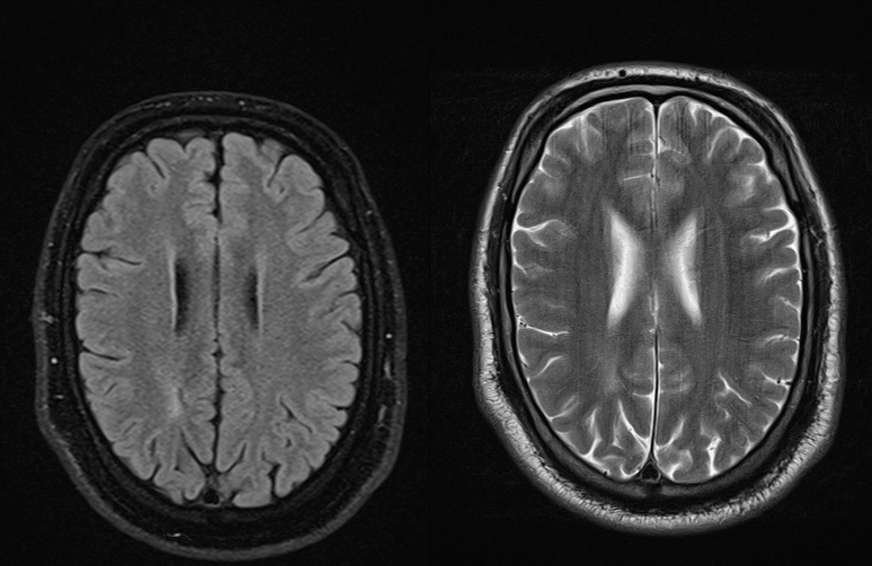

Nalaz MR (magnetna rezonanca) mozga u generaliziranim epilepsijama je obično uredan. Ponekad su u nekim formama generalizirane epilepsije vidljive periventikularne hipoksično ishemijske promjene, obično uz tada moguća pridružena i neka druga, prvenstveno kognitivna i motorička oštećenja (slika 5). Obzirom da je poznato da je MR mozga u generaliziranim epilepsijama obično uredan postavlja se pitanje da li je uvijek apsolutno indiciran. MR mozga je obavezan u slučajevima atipične kliničke slike kod pojedinih epileptičkih sindroma, izrazite farmakorezistencije ili pojave fokalnih usporenja u nalazu EEG-a.